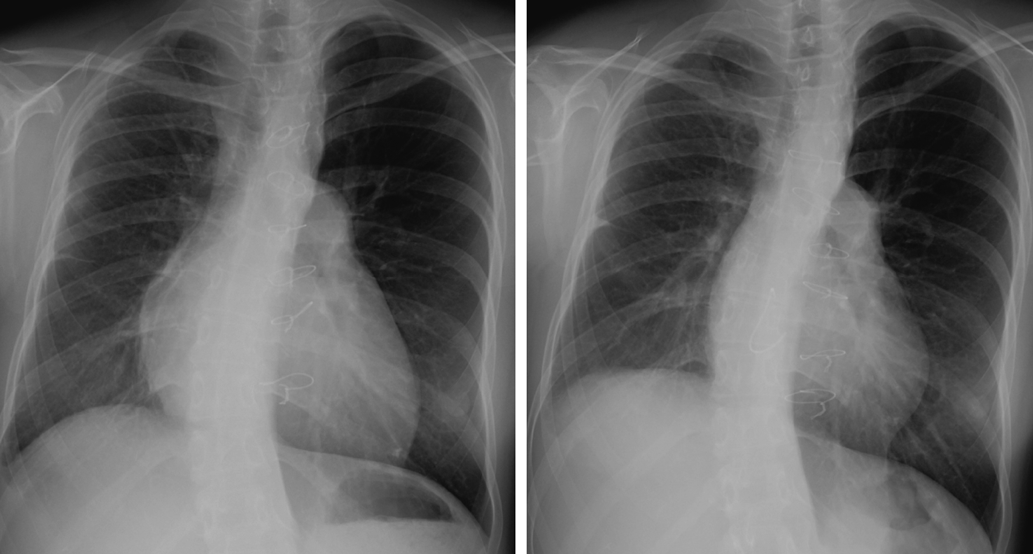

The postoperative medications including warfarin for 3 months and aspirin for 6 months as anticoagulant and antiplatelet therapies after the valve replacement were completed when she got pregnant. While, the preoperative examinations indicated good LV performance and sufficient myocardial blood supply to the coronary arteries. A myocardial perfusion scintigraphy using Technetium-99 m-labeled tetrofosmin did not indicate any significant ischemic changes both at rest and under stress (Fig. 2) with a good LV ejection fraction (LVEF) of 64%. A coronary angiography revealed a smooth blood flow through the Takeuchi route (Fig. 3).

Journal of Pediatric Cardiology and Cardiac Surgery 6(1): 15-20 (2022)

Fig. 3 A coronary angiography revealed a smooth blood flow through the Takeuchi route

Left: an ascending aortic angiography. Right: a selective coronary angiography.